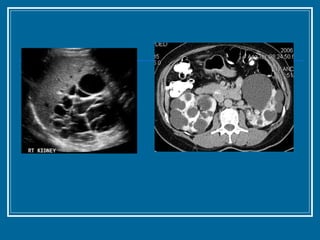

Polycystic Kidney Disease

Polycystic Kidney Disease Diagnosis Renal ultrasound  Diagnostic criteria 2 or > cysts in one kidney and at least 1 cyst in the contralateral kidney in < 30 years 2 or > cysts in each kidney age 30-59 4 or > cysts in subjects >60 years (increased frequency of benign simple cysts) CT scan or T2-weighted MRI is more sensitive in subjects <30 years of age Cerebral arteriography screening if family history of aneurysms

Polycystic Kidney DiseaseDiagnosis Renal ultrasound Diagnostic criteria 2 or > cysts in one kidney and at least 1 cyst in the contralateral kidney in < 30 years 2 or > cysts in each kidney age 30-59 4 or > cysts in subjects >60 years (increased frequency of benign simple cysts) CT scan or T2-weighted MRI is more sensitive in subjects <30 years of age Cerebral arteriography screening if family history of aneurysms